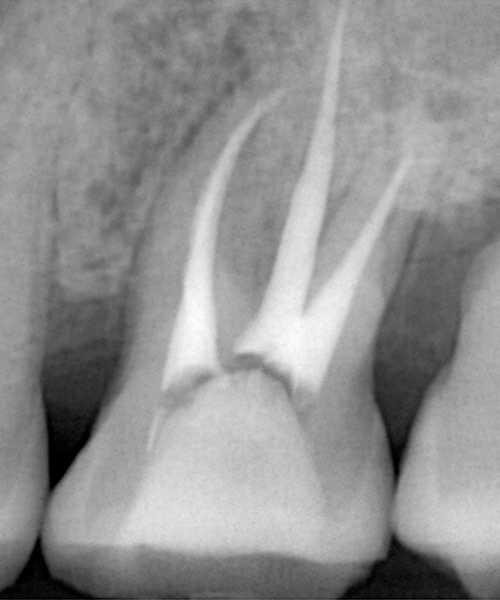

根尖性歯周炎

重度のむし歯や歯周病などを放置したために、骨の中まで炎症が進行すると炎症が歯の根の先端まで到達し、周りの骨にまで炎症が波及する「根尖性歯周炎」と呼ばれる状態になります。

また一度根管治療をおこなった歯が、根尖性歯周炎となってしまうことも多くみられます。